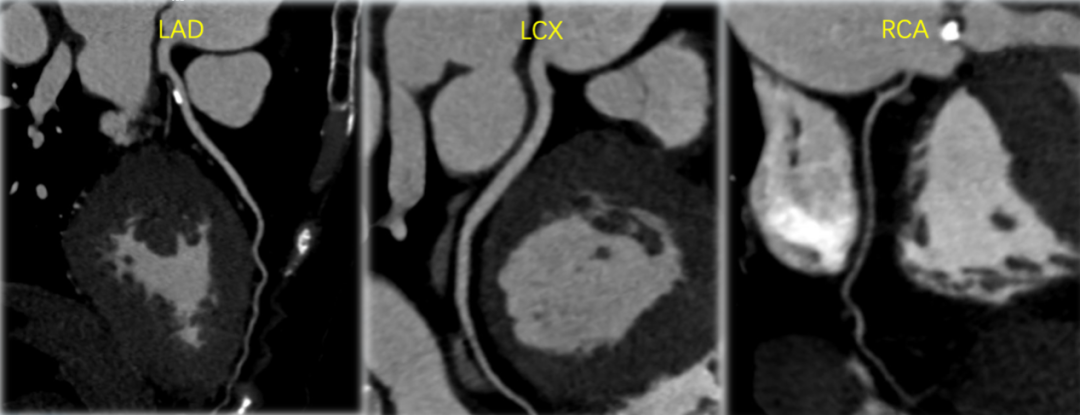

CT冠脉评估患者三支主干未见严重狭窄。前降支近段存在一30%狭窄的钙化斑块,右冠细小,为左优势型冠脉。

该名患者为Type 0型二叶瓣,右冠窦轻度钙化。瓣环最短径为20.0mm,最长径为27.7mm,平均瓣环直径为23.8mm。升主动脉较宽,平均直径40.5mm。左冠开口高度13.6mm,右冠开口高度16.3mm,冠脉阻塞风险低。外周血管钙化轻,入路情况较佳。FEops分析推荐匹配26mm瓣膜。